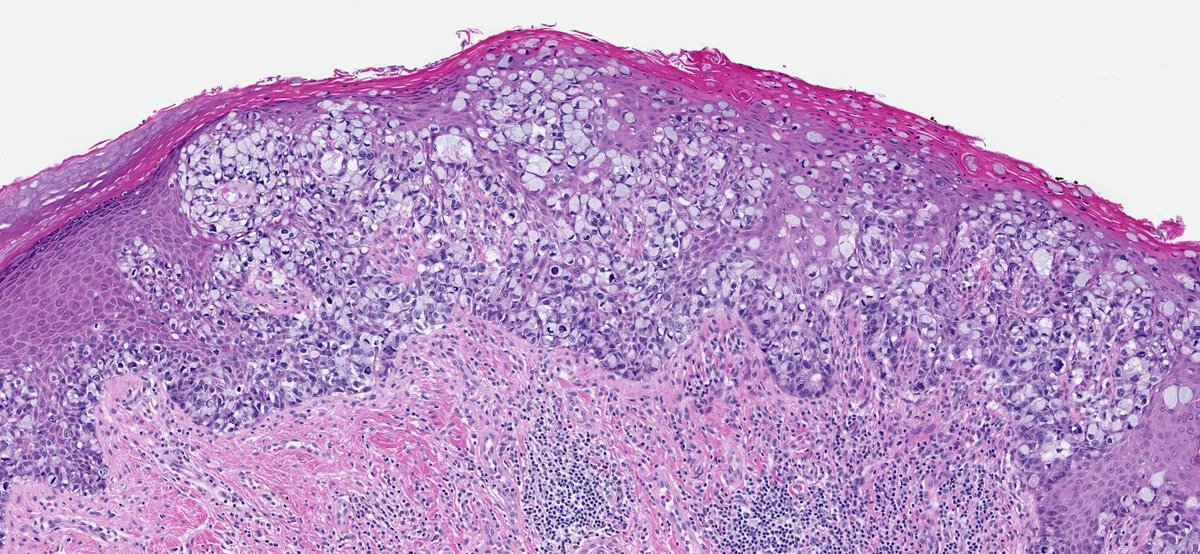

70M with parotid mass. What is your diagnosis?